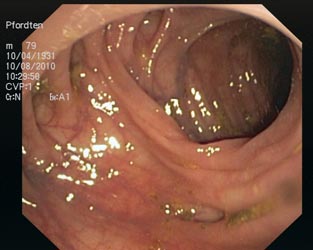

Im Darm können sich Ausbuchtungen der Darmwand (Divertikel) nach außen bilden, die in der Darmspiegelung als kleine Löcher zu erkennen sind (Bild Divertikulose). In seltenen Fällen können sich die Divertikel entzünden, dann spricht man von einer Dickdarmdivertikulitis. Die Diagnose wird durch die Symptome (Schmerzen), durch eine Bauchuntersuchung, eine Ultraschalluntersuchung (siehe Bild) und durch eine Laborunteruschung gestellt.